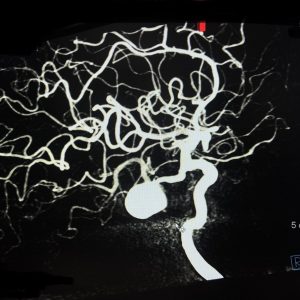

Interesting case of Persistent Trigeminal Artery large Aneurysm treated Endovascularly, International Endovascular conference SNVICON 2022 GOA

Endovascular Treatment of a Saccular Aneurysm Associated with Fenestrated Basilar Artery, BOMBAY NEUROSCIENCES ASSOCIATION at KEM Hospital

Patel HR, Pandurang BS, Nadkarni TD. Endovascular treatment of a saccular aneurysm associated with fenestrated basilar artery and proximal stenosis of vertebral artery origin-A treatment challenge. Journal of Cerebrovascular Sciences. 2021 Jan 1;9(1):38.

Photo Gallery